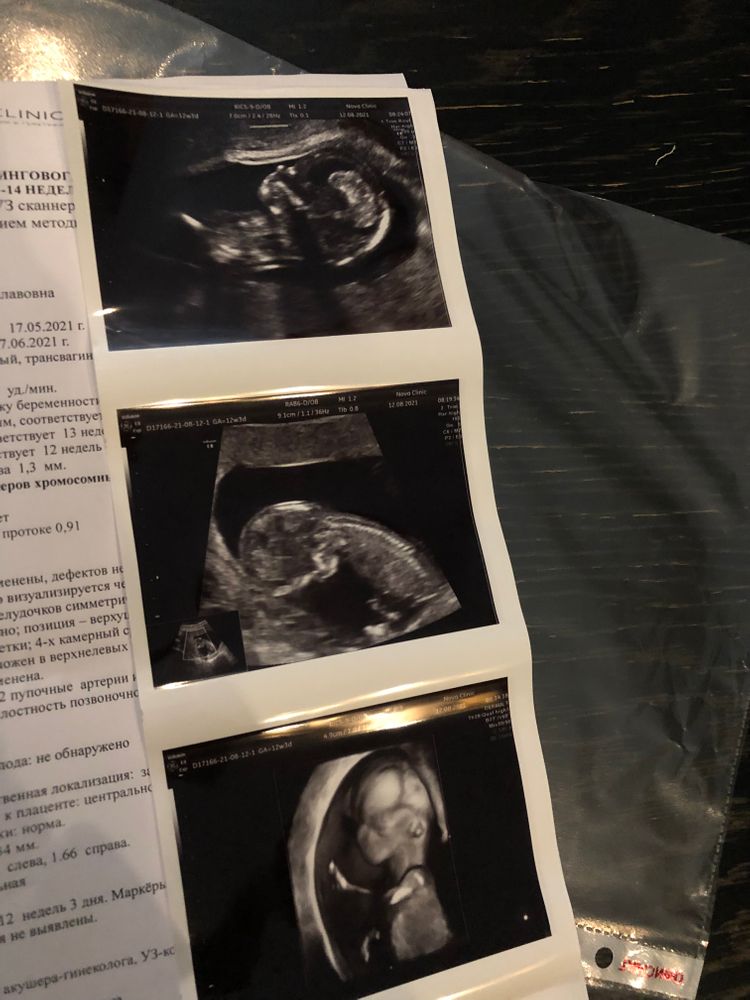

Первое скрининговое узи🐥

ну какая красота, так еще четко все видно))) поздравляю вас!))))

квитка, спасибо💋 да, действительно было видно очень хорошо) даже пальчики все хорошо просматривались))